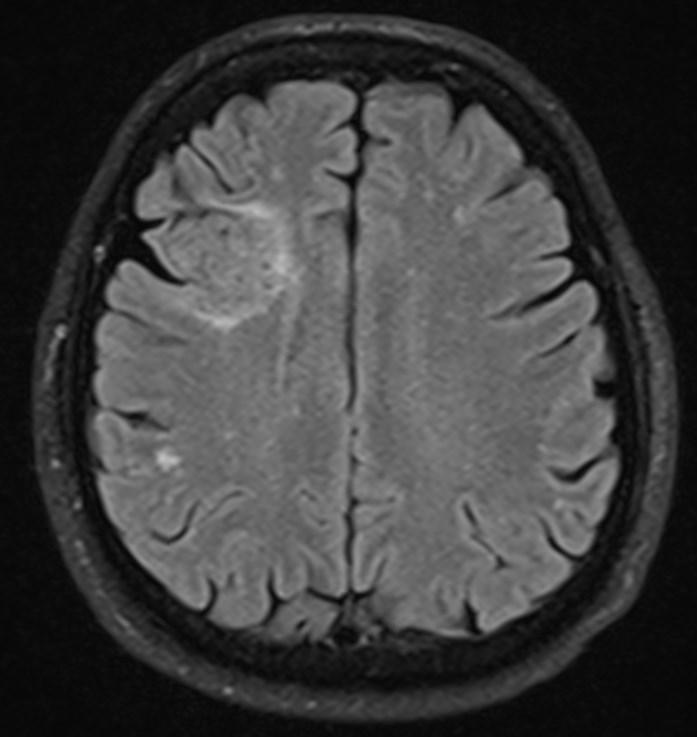

Answer: Primary hydatid cyst of right frontal lobe.

MR images revealed Gharbi type V hydatid cysts in right frontal lobe.

Gharbi classified hydatid cyst ultrasonographic images into 5 types: Type 1, walled, unilocular, anechoic; type 2, separated membranes; type 3, multisepta, daughter vesicles; type 4, heterogenic, hypo-hyperechogenic; type 5, calcification of a section of the wall or completely calcified (4). The cysts characteristically have three components: Pericyst, Exocyst, and Endocyst.